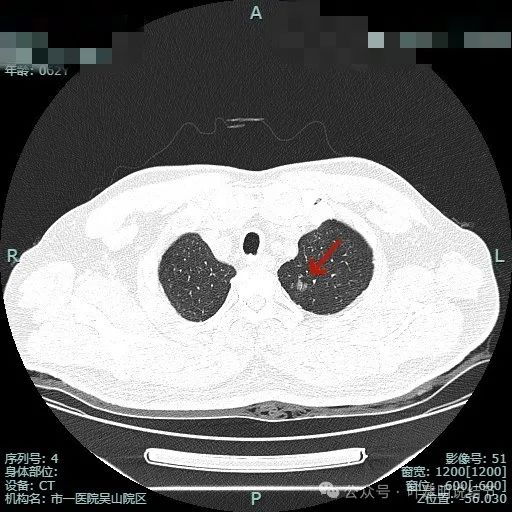

先看非薄层影像:

左上病灶出现,密度较淡,但轮廓较清。